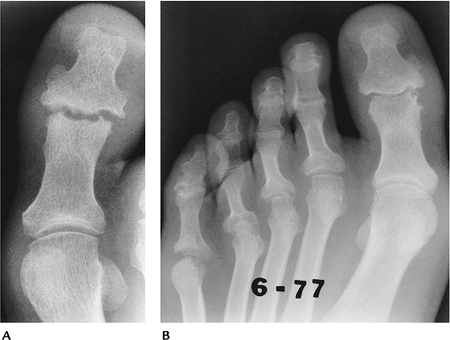

FIGURE 13-4 Psoriatic arthritis involving the foot. (A)

Osteolysis and reparative new bone in the first and third DIP joints. The erosive changes in the first DIP is a common location for psoriatic arthritis. (B) Advanced changes in the DIP joints of the lesser toes with no bone demineralization. |